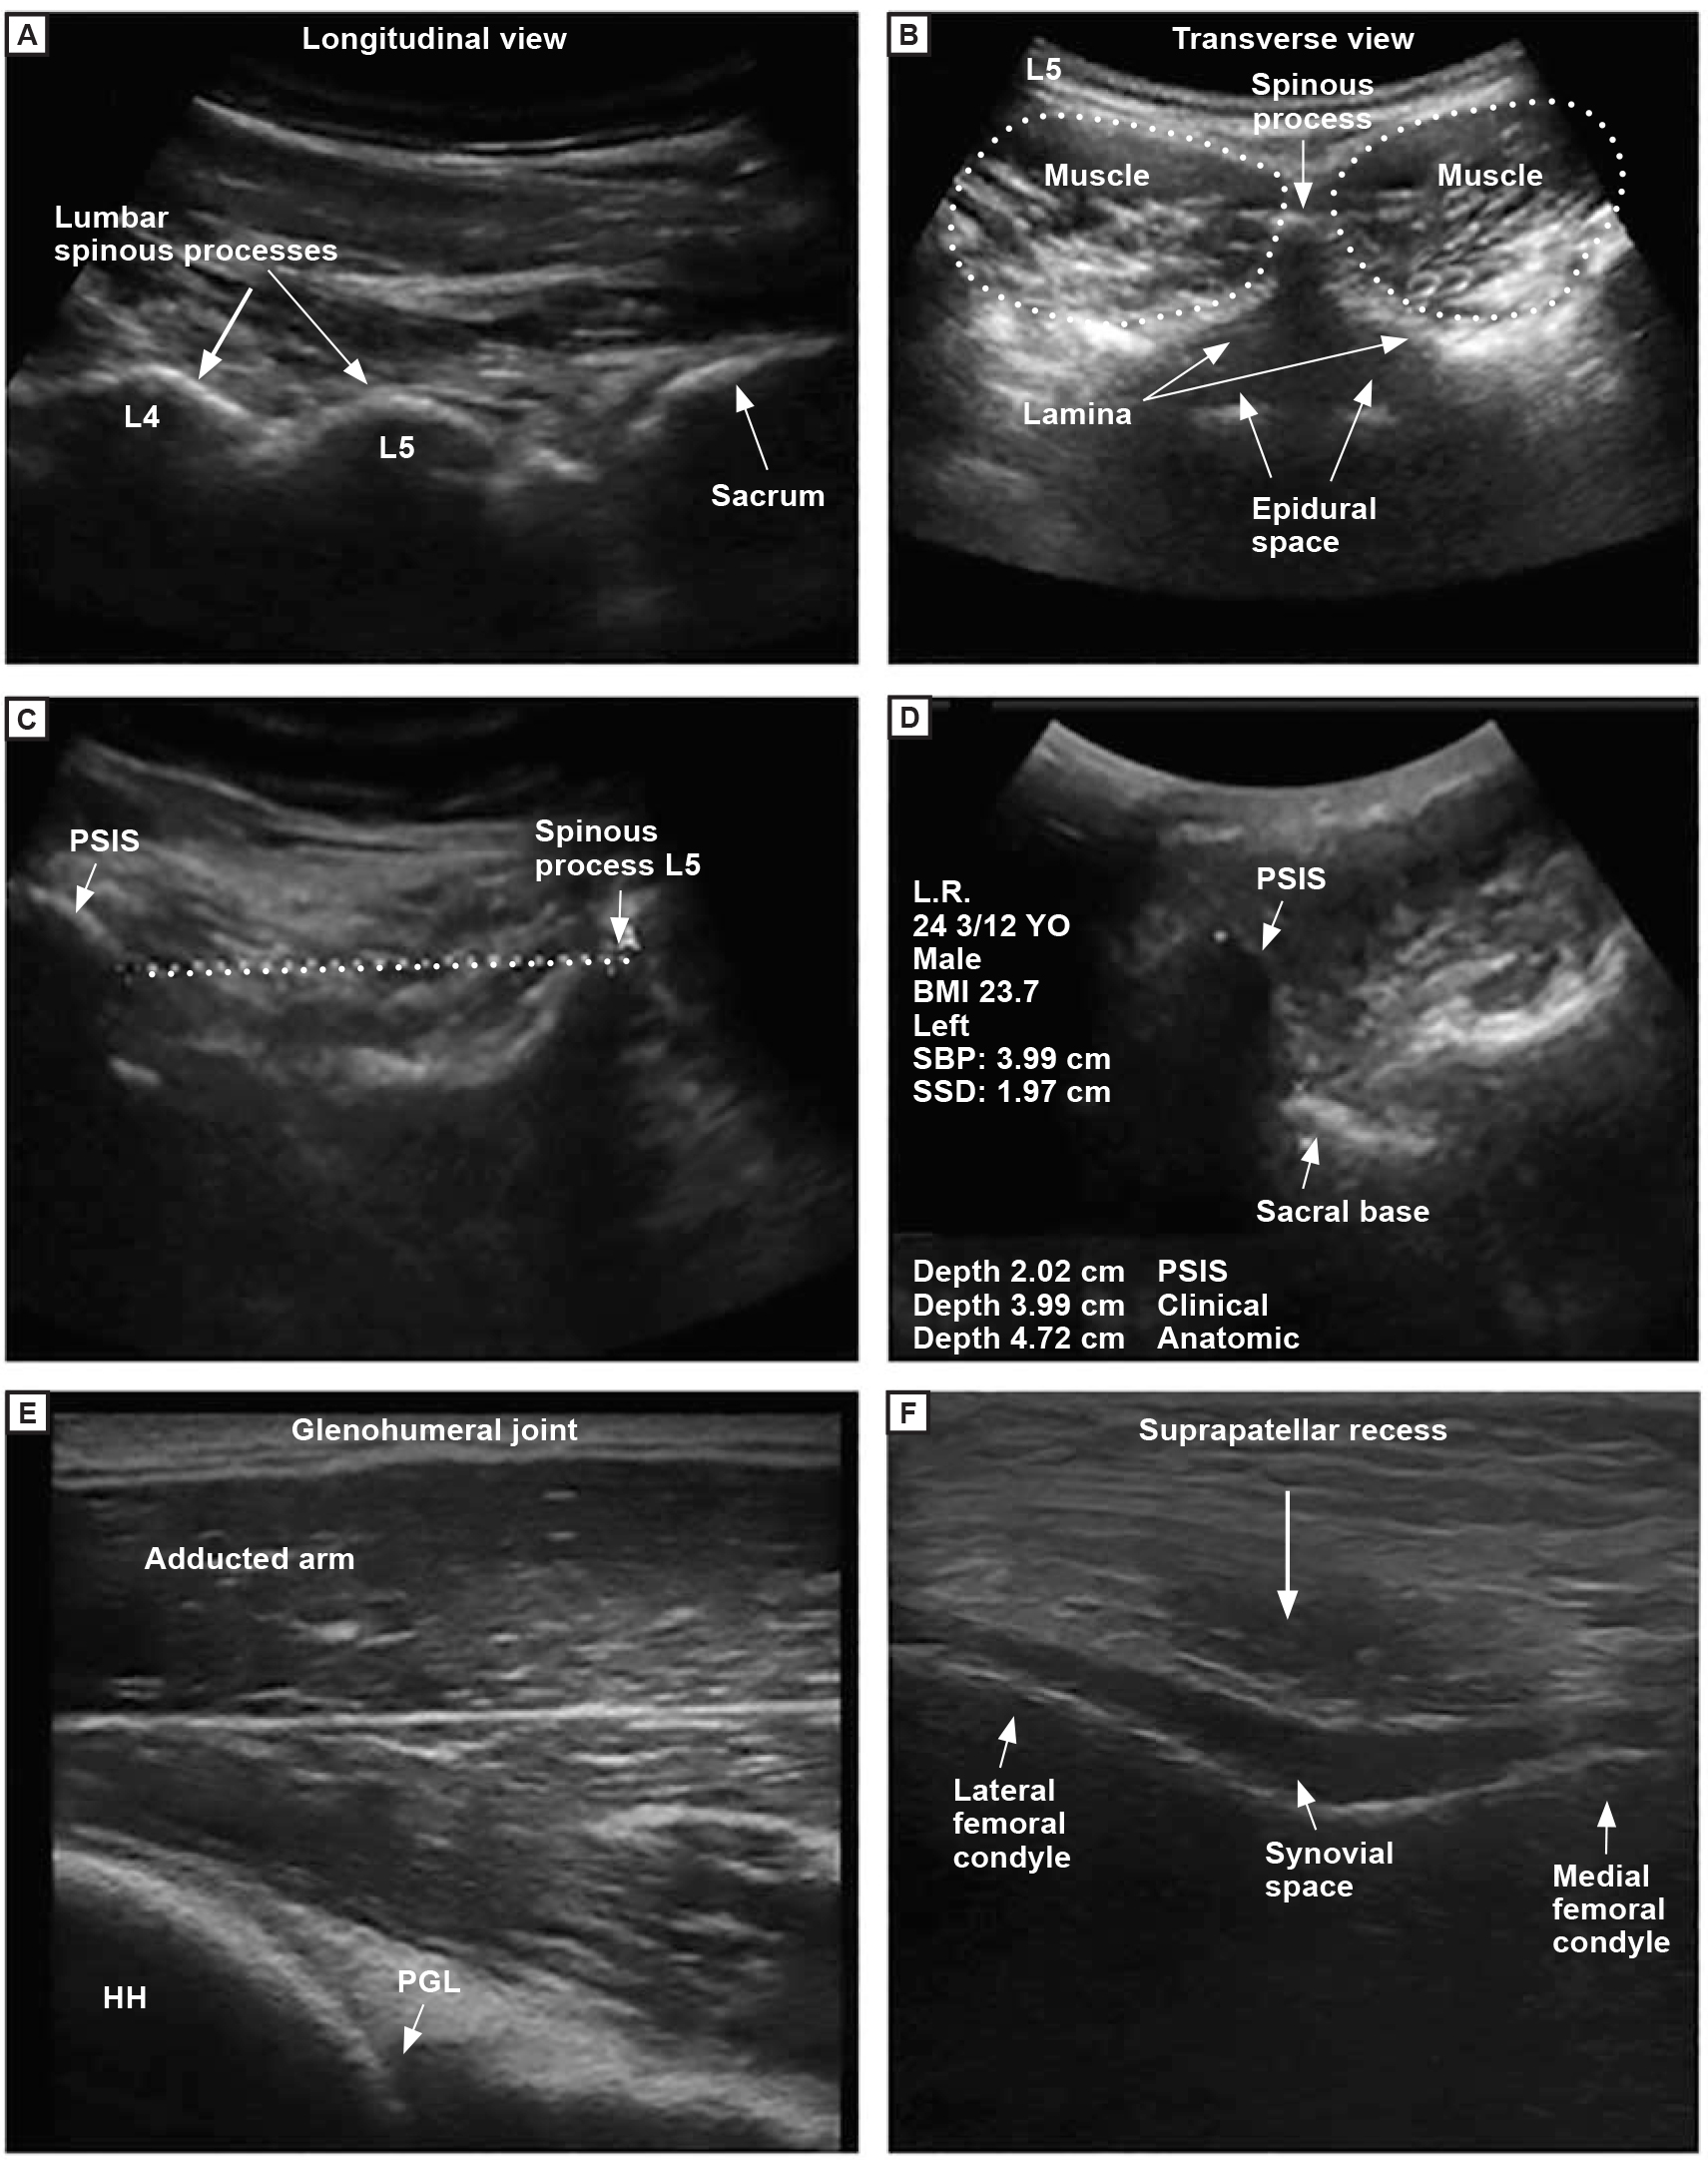

The assignments focused on identifying structures of interest, making annotations, and measuring musculoskeletal structures either at rest or under mechanical stress (Figure). Students were given 30 minutes to complete each assignment. During this time, they were required to identify target structures; acquire the images, which they labeled and saved on an external memory card; and record the demographic data of the student being scanned, including his or her initials, sex, age, and body mass index. Students then submitted the images electronically through a learning management system. Grading criteria included proper labeling of the structures of interest, proper measurements (if applicable), and demographic information obtained.

Examples of ultrasonography images taken by first- and second-year osteopathic medical students. (A) Lumbar spine in the longitudinal view. (B) Lumbar spine in the transverse view. (C) Spinous process of the fifth lumbar vertebra (L5) and posterior superior iliac spine (PSIS) in the transverse view. (D) Sacral base position and sacral sulcus depth. (E) Posterior glenohumeral joint with the arm in the adducted position. (F) Suprapatellar recess in the transverse view (sunrise view). Abbreviations: HH, humeral head; PGL, posterior glenoid labrum.

The assignments for first-year students included scanning the cranial and cervical structures and the thoracic, lumbar, and sacral regions (Table 1). For the first assignment, spinal landmarks, students were required to obtain images of the lumbar vertebrae and sacrum. The images had to include a longitudinal view of the spinous processes of the fourth and fifth lumbar vertebrae (L4 and L5) and the base of the sacrum, as well as a transverse view of the lumbar vertebrae with labeled spinous processes, laminae, and erector spinae muscles. For the second assignment, sacral landmarks, students were required to locate the spinous process of L5, identify the posterior superior iliac spine (PSIS) directly lateral to the spinous process of L5, measure the distance between the skin and the sacral base (sacral base position), and measure the distance between the skin and the tip of the PSIS. Students then used this information to define the distance between the tip of the PSIS and the sacral base position to determine the sacral sulcus depth. For the third assignment, costotransverse joint, students identified the joint of the first thoracic vertebra (T1) and the first rib. Students were required to identify T1 in the transverse view, including the spinous process and laminae, and to identify the joint of the transverse process of T1 and the first rib. For the fourth assignment, craniocervical landmarks, students had to find the atlas (first cervical vertebra [C1]), its posterior arch, and the vertebral artery and vein.

Assignments for second-year students included scanning of the glenohumeral joint and the suprapatellar recess (Table 2). For the first assignment, the glenohumeral joint, students obtained 2 images of the joint in the posterior view, 1 with the arm in the anatomical position and the other with the arm in the adducted position. Students were required to label the humeral head and posterior glenoid labrum and to measure the glenoid labrum in each position. For the second assignment, suprapatellar recess, students obtained 3 images. The first image was of the flexed knee in the longitudinal view and had to include the quadriceps tendon, patella, suprapatellar recess, synovial space, and distal femur. The second image was of the flexed knee in the transverse view and had to include the medial femoral condyle, lateral femoral condyle, and synovial space (sunrise view). The third image was also in the transverse view but included the suprapatellar recess and synovial space.